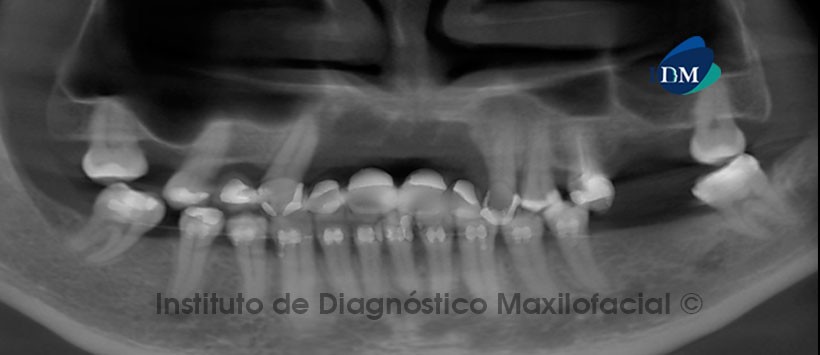

Paciente masculino de 52 años de edad que es referido a Imágenes Digitales (COREF) en Santo Domingo, para la evaluación previa a un tratamiento rehabilitador. La reformación panorámica nos muestra la pérdida severa del proceso alveolar en el sector anterosuperior, que se extiende desde la región de la pieza 13 hasta la región de la pieza 23 y desde la cima del reborde alveolar hasta las inmediaciones del piso de las fosas nasales. (Fig. 1).